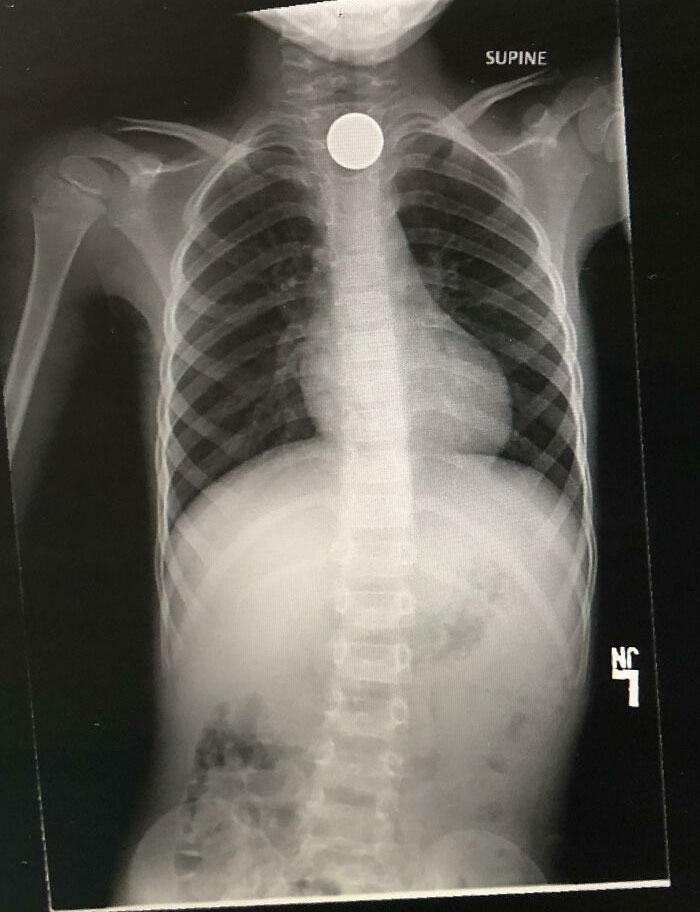

My Kid Swallowed A Penny While Showing His Little Brother How He Accidentally Swallowed A SIM Key The Day Before

Son Decided To Swallow A Nickel And Turn $.05 Into $4400.00